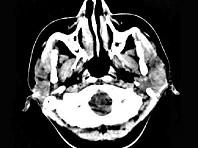

问题 女,28岁,左耳前肿块34月余,PE:左侧耳前可触及肿块,境界尚清、质硬、活动度尚可,CT如图所示,最可能诊断为()

选项 A.神经纤维瘤 B.腮腺恶性混合瘤 C.腮腺腺淋巴瘤 D.副神经节瘤 E.腮腺混合瘤

答案 E